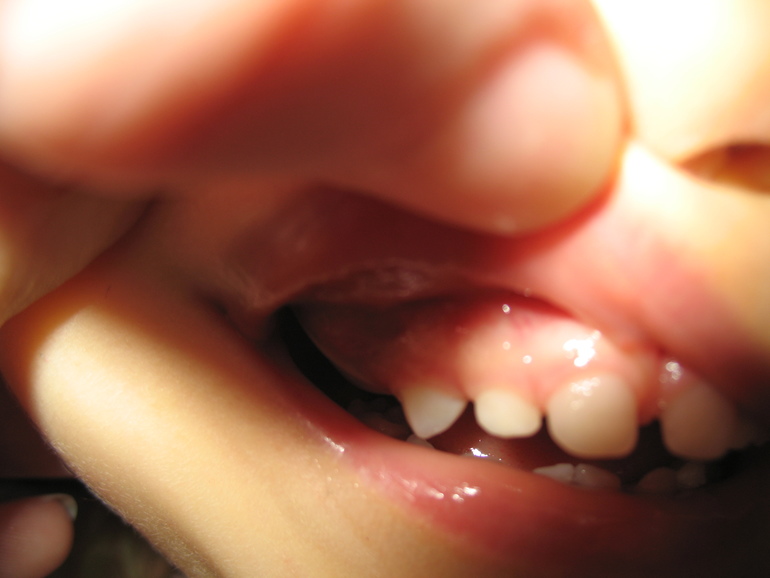

Набухла десна, с синевой. Ребенку 2 года 3 месяца.

В пятницу вечером обнаружила у ребенка на врехней правой части десны припухлость(выглядит как шишка), напугало, то что было на месте между резцом и уже вылезшим коренным зубом. Шестерок у нас еще нет.

, прихожу с работы поздно, зубы чистить дает не всегда мне.. ). Что это может быть? Какие методы лечения? Очень переживаю. Вид десны пугает. Нужны ли какие-то срочные действия? Врач, которая нас осматривала, сказала, что срочные действия не нужны, мазать калгелем саму десну и вот снимок сделать. Покажет ли еще что-то прицельный снимок? Не хочется еще ребенка мучить зря, она давилась от пластинки, плакала. Если нужен на какую область обратить внимание? Еще вспомнила, что она как то месяц- полтора назад падала, и сильно стукнулась, примерно в той области, немножко была разбита губка изнутри. Вы беретесь за такае случаи? Если нет, подскажите нам врача!!! заранее огромное спасибо!